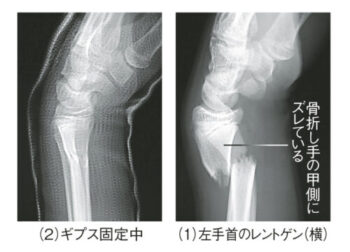

整形外科としては、足が固定されているため転倒した時に手を着くことから、肩・肘・手首の怪我が多いのが特徴です。このレントゲンはフロントサイドで手の平から手を着いたため、手首の骨折が起こりました⑴。⑵が整復してギプス固定を行った状態です。中には手術が必要な外傷もあります。